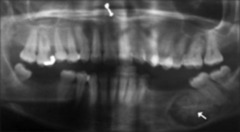

Papillion-Lefevre

-Genetic -tooth mobility, pockets,PALMOPLANTAR HYPERKERATOSIS -profuse inflammatory infiltrate of soft dental tissues